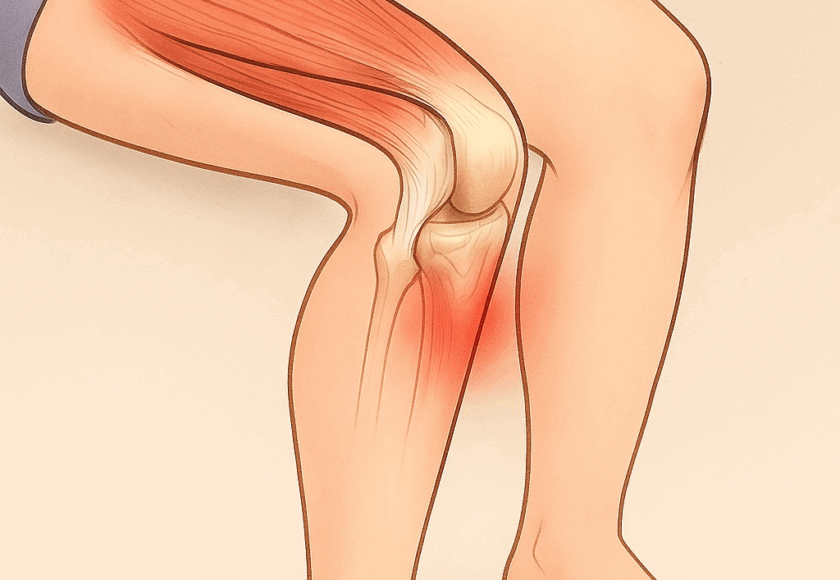

膝のお皿(膝蓋骨)のすぐ下、スネの骨(脛骨)にある

出っ張り部分が強く引っ張られることで炎症が起こり、

膝の下が腫れて痛みを感じます。特に走る・跳ぶ動作を

特に太ももの前の筋肉(大腿四頭筋)が硬くなると、膝の下にある脛骨粗面が強く引っ張られ、炎症や痛みの原因になります。

- 硬くなった大腿四頭筋やふくらはぎを緩めて、膝への負担を減らす